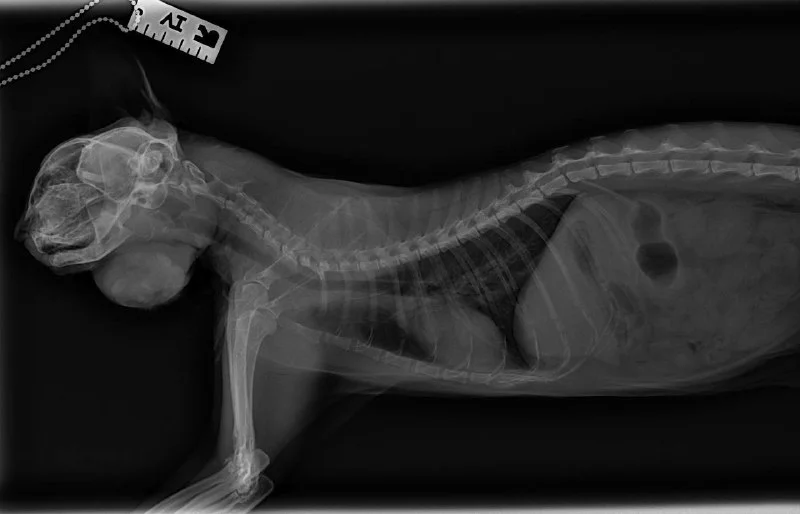

Так выглядит качественная стерилизация у девочек